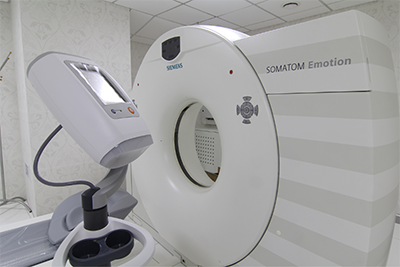

Новейшее оборудование ведущих мировых производителей

Такой результат достигается благодаря наличию в усовершенствованном аппарате нескольких спиральных датчиков, сканирующих нужную зону послойно и передающих все данные в объемное изображение на экран компьютера.

Процедура проходит в течение 20–30 минут. Все это время пациент находится в положении лежа на специальной кушетке, которая располагается внутри аппарата. Для исключения движений голова фиксируется ремнями и валиком. В процессе исследования сканируемое изображение появляется на экране монитора, затем может быть перенесено на фактические снимки или цифровой носитель.

В клинике "Евромед" в Новосибирске проводится МСКТ носа на современном оборудовании. Пациентам клиники доступна консультация специалистов с высокой квалификацией и многолетним опытом работы. Записаться на диагностику можно в любое время на сайте медицинского центра или по контактному телефону.